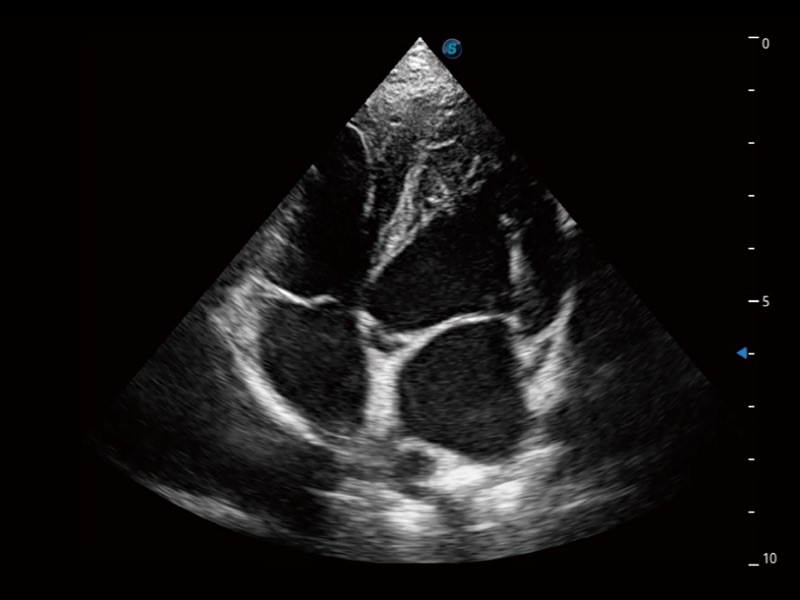

ProPet 70 进一步提升了微米成像算法,更加注重对基础原始图像的还原和保留,在有效减少斑点噪声、增强组织边界显示的同时,避免过度优化丟失真实的解剖信息。

为精细结构及组织边缘提供高清晰度的图像和更大的成像视野。帮助减轻医生的用眼疲劳,快速精准获得测量的数据。